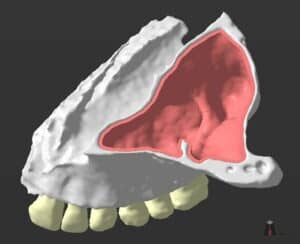

Note here that although the data we aquire from a CBCT are 3-dimensional, in reality the representation is still 2D: we only see it in a flat screen. To recreate a truly 3D representation you will need to 3D print the data from the CBCT. This is actually a very powerfull teaching medium, which we have often utilised in complex surgeries. 3D printing the anatomy prior to surgery allows you to test different techniques and access points with safety, before you choose the best way to go in (or sometimes to not go in at all).

A Challenging surgical case with a complex of vertical and horizontal septa in the posterior sinus. Segmentation of the 3D radiographical and optical data and 3D printing in multiple layers from AMMA Ltd Hong Kong, has allowed for an accurate representation of the anatomy where multiple surgical access approaches were tested.